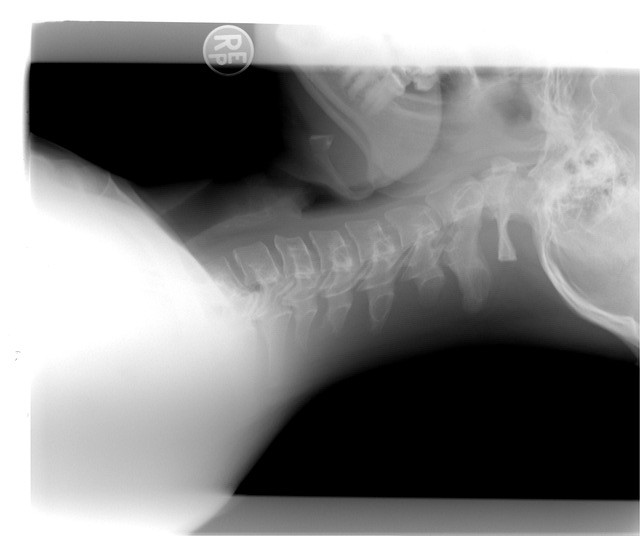

A vertebral fracture is a break, crack or collapse of one or more of the bones (vertebrae) in the spinal column. These fractures may occur as a result of high-energy trauma, such as a vehicle collisio...